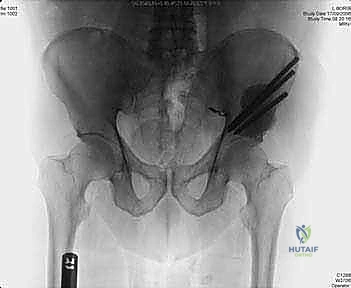

- التصوير بالأشعة السينية (X-rays): الفحص المبدئي لرصد أي تآكل أو تدمير في البنية العظمية للحوض ومفصل الورك.

- التصوير المقطعي المحوسب (CT Scan): يقدم صوراً ثلاثية الأبعاد تُظهر بدقة متناهية مدى تدمير القشرة العظمية، وهو الفحص الأهم للتخطيط الجراحي وتحديد خطر حدوث الكسور المرضية.

التقييم البيوميكانيكي هو تخصص دقيق. يستخدم الدكتور هطيف معايير علمية (مثل معايير هارينغتون Harrington Criteria) لتحديد ما إذا كان عظم الحُق أو الحوض على وشك الانهيار.

* الكسر المرضي الفعلي: إذا انكسر الحوض بالفعل، فإن الجراحة ضرورية لتثبيت العظم المكسور والسماح للمريض بالحركة.

* الكسر الوشيك: إذا أظهرت الأشعة المقطعية أن الورم قد دمر أكثر من 50% من قشرة العظم المحيطة بمفصل الورك، أو تسبب في ألم شديد عند تحميل الوزن، فإن التدخل الاستباقي لمنع الكسر أسهل وأكثر نجاحاً من محاولة إصلاح كسر قد حدث بالفعل.

2. عملية إعادة بناء هارينغتون (Harrington Reconstruction)

تُستخدم هذه التقنية المتقدمة عندما يكون الورم قد دمر منطقة "الحُق" (سقف مفصل الورك).

* يقوم الدكتور هطيف بإدخال دبابيس معدنية ملولبة قوية (Threaded Pins) عبر العظم الحرقفي السليم لتصل إلى منطقة الحُق.

* يتم تشكيل كتلة من الإسمنت العظمي حول هذه الدبابيس لإنشاء "سقف صناعي" جديد ومتين لمفصل الورك.

* بعد ذلك، يتم تركيب مفصل ورك صناعي كامل (Total Hip Arthroplasty) يرتكز على هذا السقف الإسمنتي القوي، مما يسمح للمريض بالمشي مجدداً دون ألم.